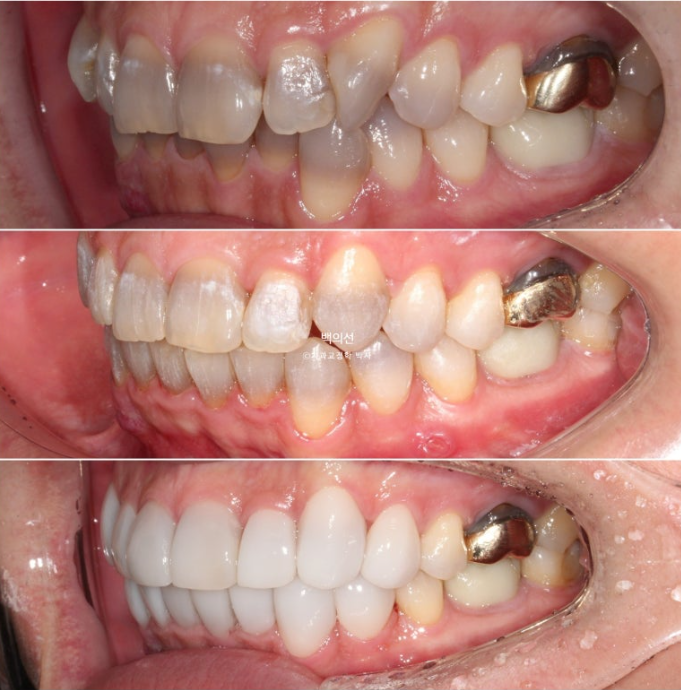

This patient came in for no-prep laminate treatment in December 2023.

They wanted all teeth, from the canines back to the premolars, both upper 8 and lower 8, covered with laminate.

The discoloration is severe, with a fairly deep gray tone.

However, as you can see from the front, the canine crowding means laminate treatment would be difficult unless orthodontic treatment is done first.

In the lower front teeth, there are varying heights in addition to the canine crowding.

Now let’s compare the initial visit, after orthodontic treatment, and after Gelami in sequence.

23.12~25.06